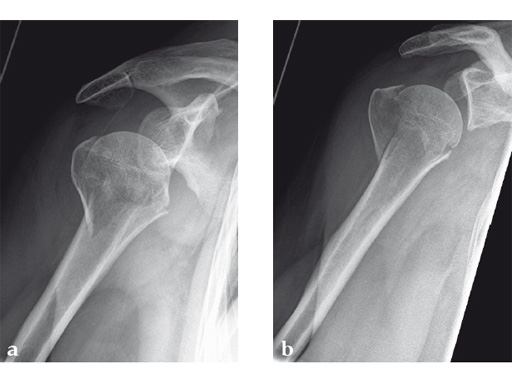

Case 1: A three-part valgus impacted fracture of the proximal humerus in a 47-year-old woman.